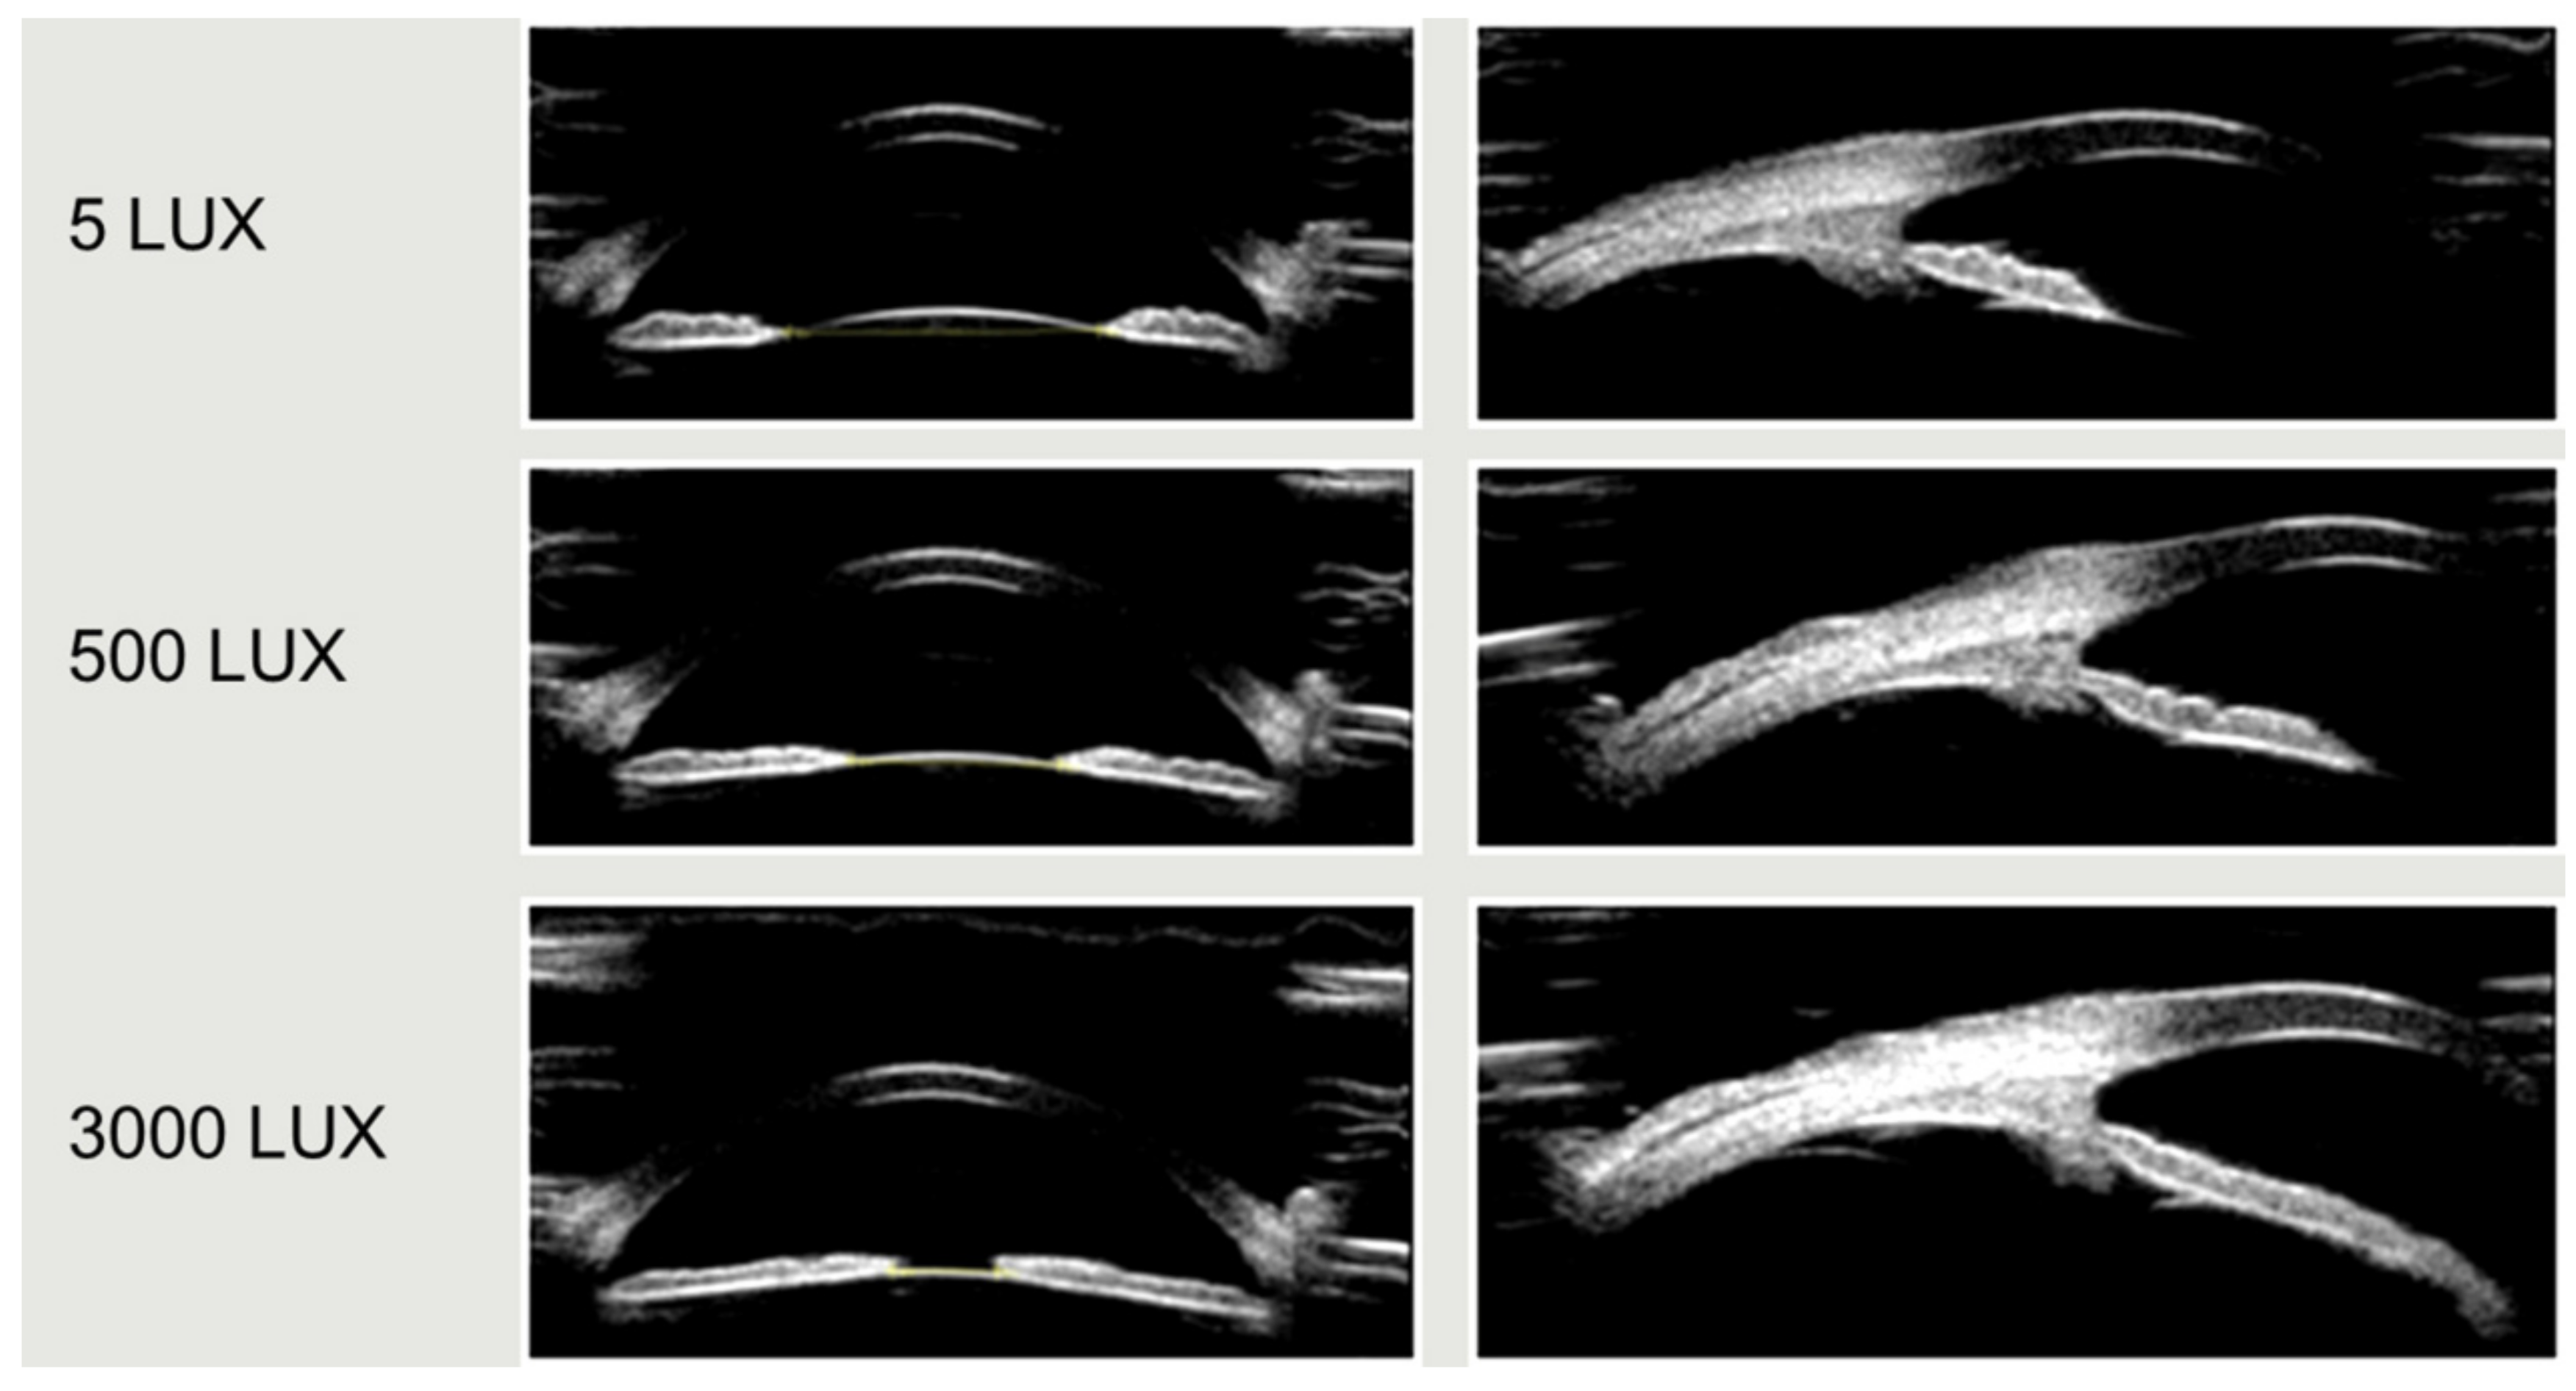

The results from the seven repeated measurements also showed that the amplitude of accommodative response change was larger in the dynamic lighting group under different light intensities, and this amplitude was statistically significant (p < 0.001). However, the change was small in the static lighting group with fixed light intensity, and the change was not statistically significant. In this study, the interaction between the light mode and the accommodative response was statistically significant (p < 0.001) (Table 2, Figure 3). Figure 4 showeds UBM image samples of the anterior segment of a subject’s eye which was captured under different light intensities while the stimulus of accommodation and convergence remained the same.

Figure 4. UBM image samples of the anterior segment of a subject’s eye under illuminations of 5500 and 3000 lux, respectively. The pupil shrinks significantly as the light increases.